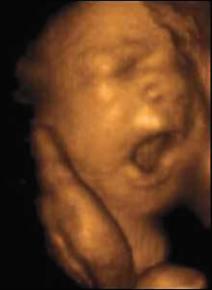

런던 크리에이트 병원의 스튜어트 캠벨 교수가 만든 이 스캐너는 12주된 태아가 자궁 속에서 걸어다니고,손가락을 빨며,하품하는 모습을 생생하게 잡아내고 있다. 태아가 발육 초기에 하품을 하거나 눈을 비비는 ‘복잡한’ 행동을 한다는 사실은 캠벨 교수의 스캐너에 의해 처음 발견됐다고 BBC는 전했다.